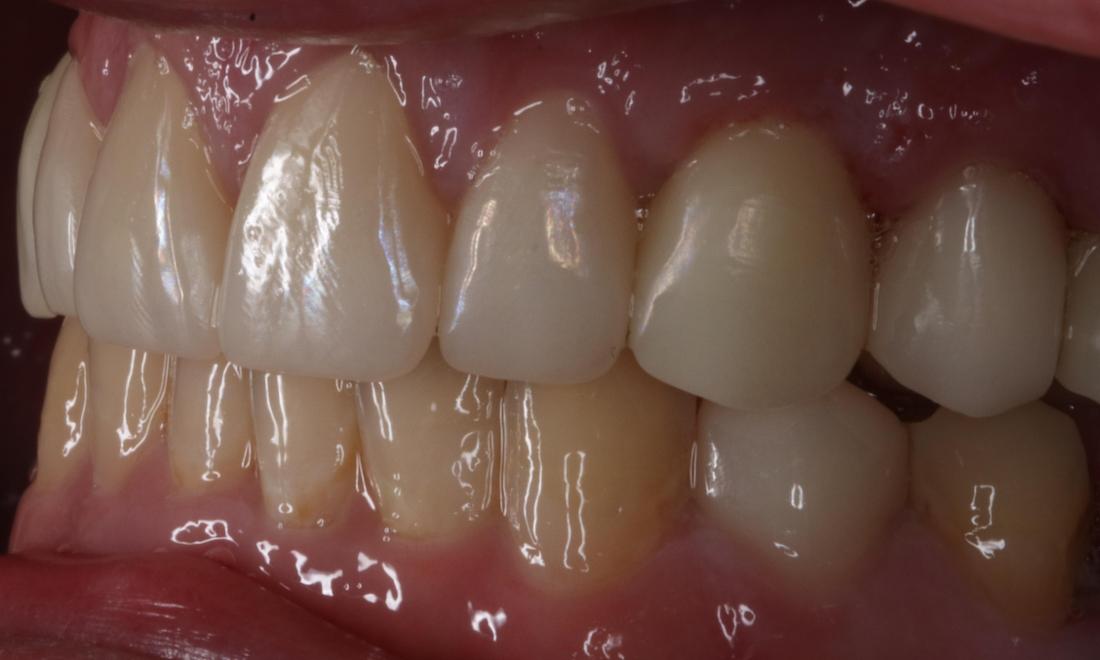

After a long journey to sobriety, this patient was ready to get his mouth healthy along with the rest of his body.  He was ready to smile with his kids again and jumpstart his new career.

Close up of mouth from a side view before a complete smile makeover, nashville tn Close up of mouth from a side view after a complete smile makeover, nashville tn